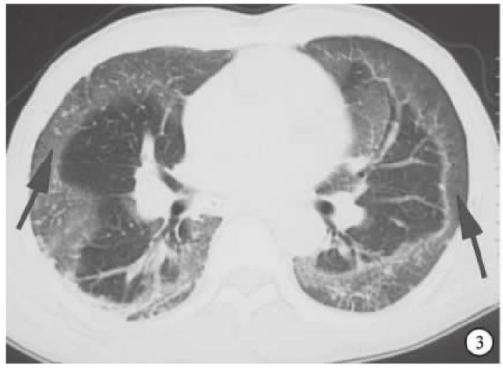

典型的新冠肺炎影像学并不难,诊断的关键是:

早期出现小斑片或间质性改变,常有磨玻璃阴影;

病灶主要位于胸膜下。随着病情进展,病灶常为双肺多发。

随着病情进展,CT失去特异性,不容易鉴别与一般的肺炎。

▎间质性肺炎

很多间质性肺炎都会表现为胸膜下为主的病灶,特别是隐源性机化性肺炎,需要结合临床表现具体分析。